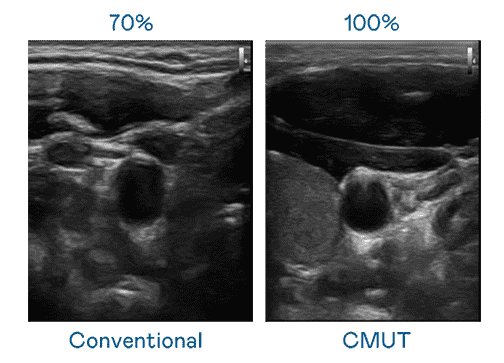

CMUT 技术是一种用电容式微机电元件来产生超音波讯号的技术。。。与传统 PZT 压电式技术相比,,CMUT 频宽增加 30%,,更宽频的超音波讯号让影像解析度大幅提升,,,,是实现高影像品质医疗超音波扫描、、、、促进精准医疗发展的关键技术。。。

超音波影像的解析度高低,,,首先取决于探头能发出的讯号频宽。。。。银河集团 CMUT 可提供高清晰的超音波讯号,,,提供高频宽、、、高灵敏度、、、影像纹理细节更高的超音波影像,,,,协助医护人员缩短影像判读时间及利用精准的医疗影像进行诊断。。。。